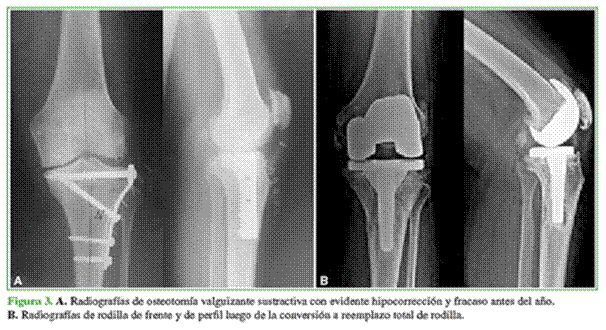

Con respecto al abordaje, en rodillas con OTA de apertura, fue pararrotuliano medial, a través del cual se retiró el material de osteosíntesis, ya que se obtuvo un acceso directo, y se realizó la artroplastia (Figura 1); en cambio, en la OTA de cierre que presentaban placa y tornillos, se realizaron dos abordajes independientes: uno sobre la cicatriz lateral para retirar la osteosíntesis y otro longitudinal anterior a través del cual se realizó el RTR, siempre dejando un espacio mínimo de 5 cm entre ambas incisiones. Como alternativa, en tres pacientes, se decidió retirar solo los tornillos proximales de la osteosíntesis a través de incisiones pequeñas para liberar el segmento proximal de la tibia y colocar el componente tibial dejando la osteosíntesis in situ (Figura 2).

Se utilizaron vástagos tibiales en siete casos con la finalidad de sobrepasar la zona de debilidad generada por la OTA (Figura 3). Además, se colocó un vástago en un paciente con retraso de la consolidación en el sitio de la OTA y en otro con un valgo severo de 25° en el que se utilizó una prótesis constreñida.